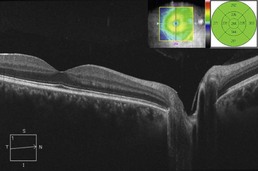

Figure 11.3.3 OCT in a case of sarcoid anterior uveitis shows subtle cystoid macular edema (CME), which was clinically symptomatic. The associated thickness map (inset) shows generalized parafoveal thickening, which gives a better overall sense of the CME than the isolated line scan. There is a strand of hyaloid that is visible, which is not of any clinical significance.